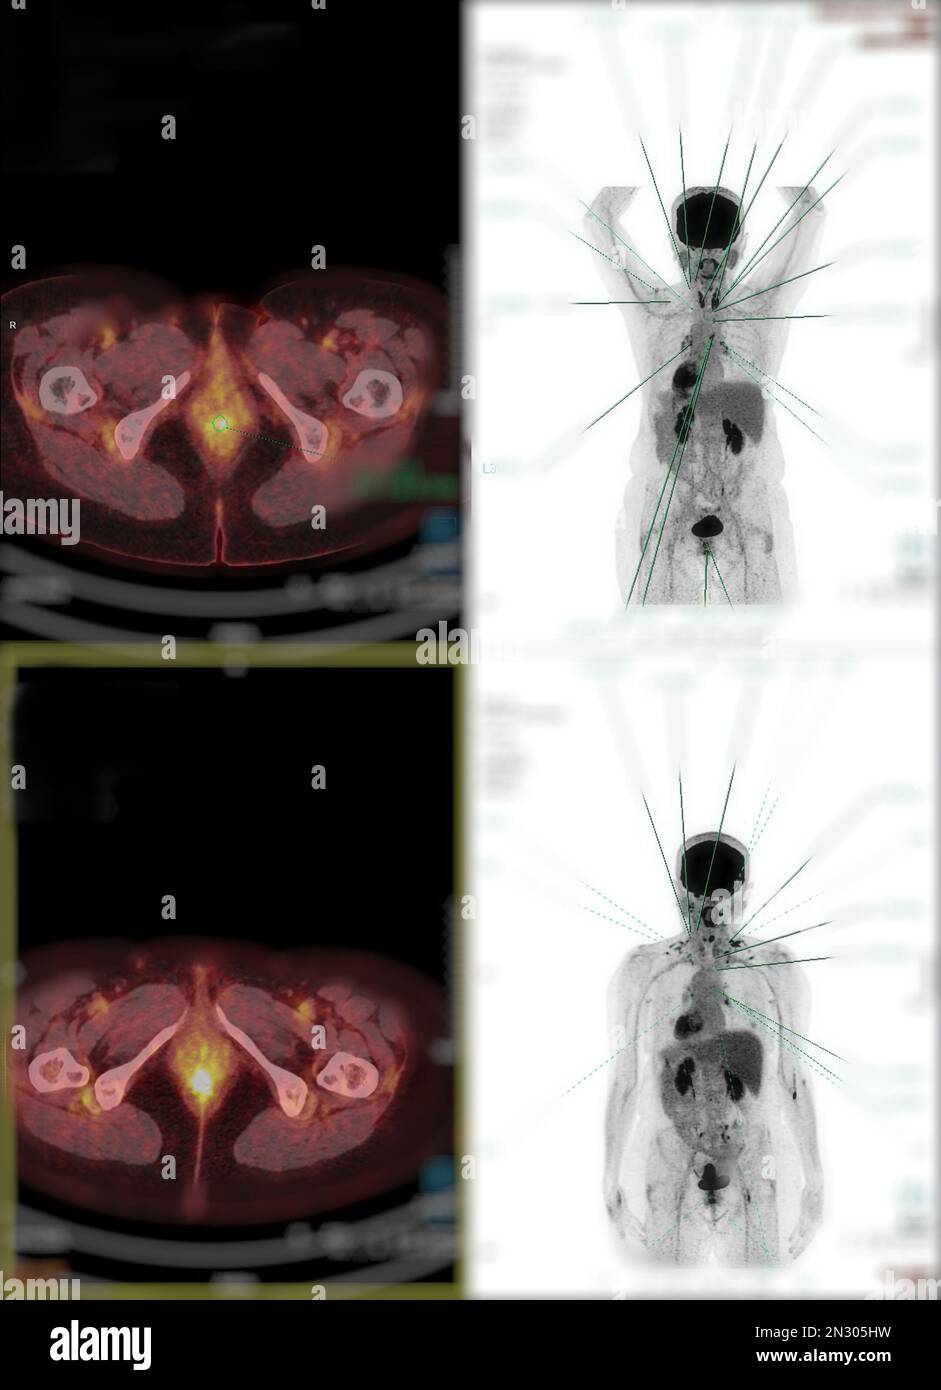

From www.alamy.com

Positron emission tomography (PET) CT scan uses a radioactive drug Autoradiography And Positron Emission Tomography This is a text on cerebral and myocardial imaging using positron emission tomography and autoradiography using positrons emission. Positron emission tomography is almost unique in determining quantitatively from images the function of body processes not available from. Rapid development of labeling chemistry and generation of new chemical entities for biologic interactions via combinatorial. This text by phelps, mazziotta, and schelbert,. Autoradiography And Positron Emission Tomography.